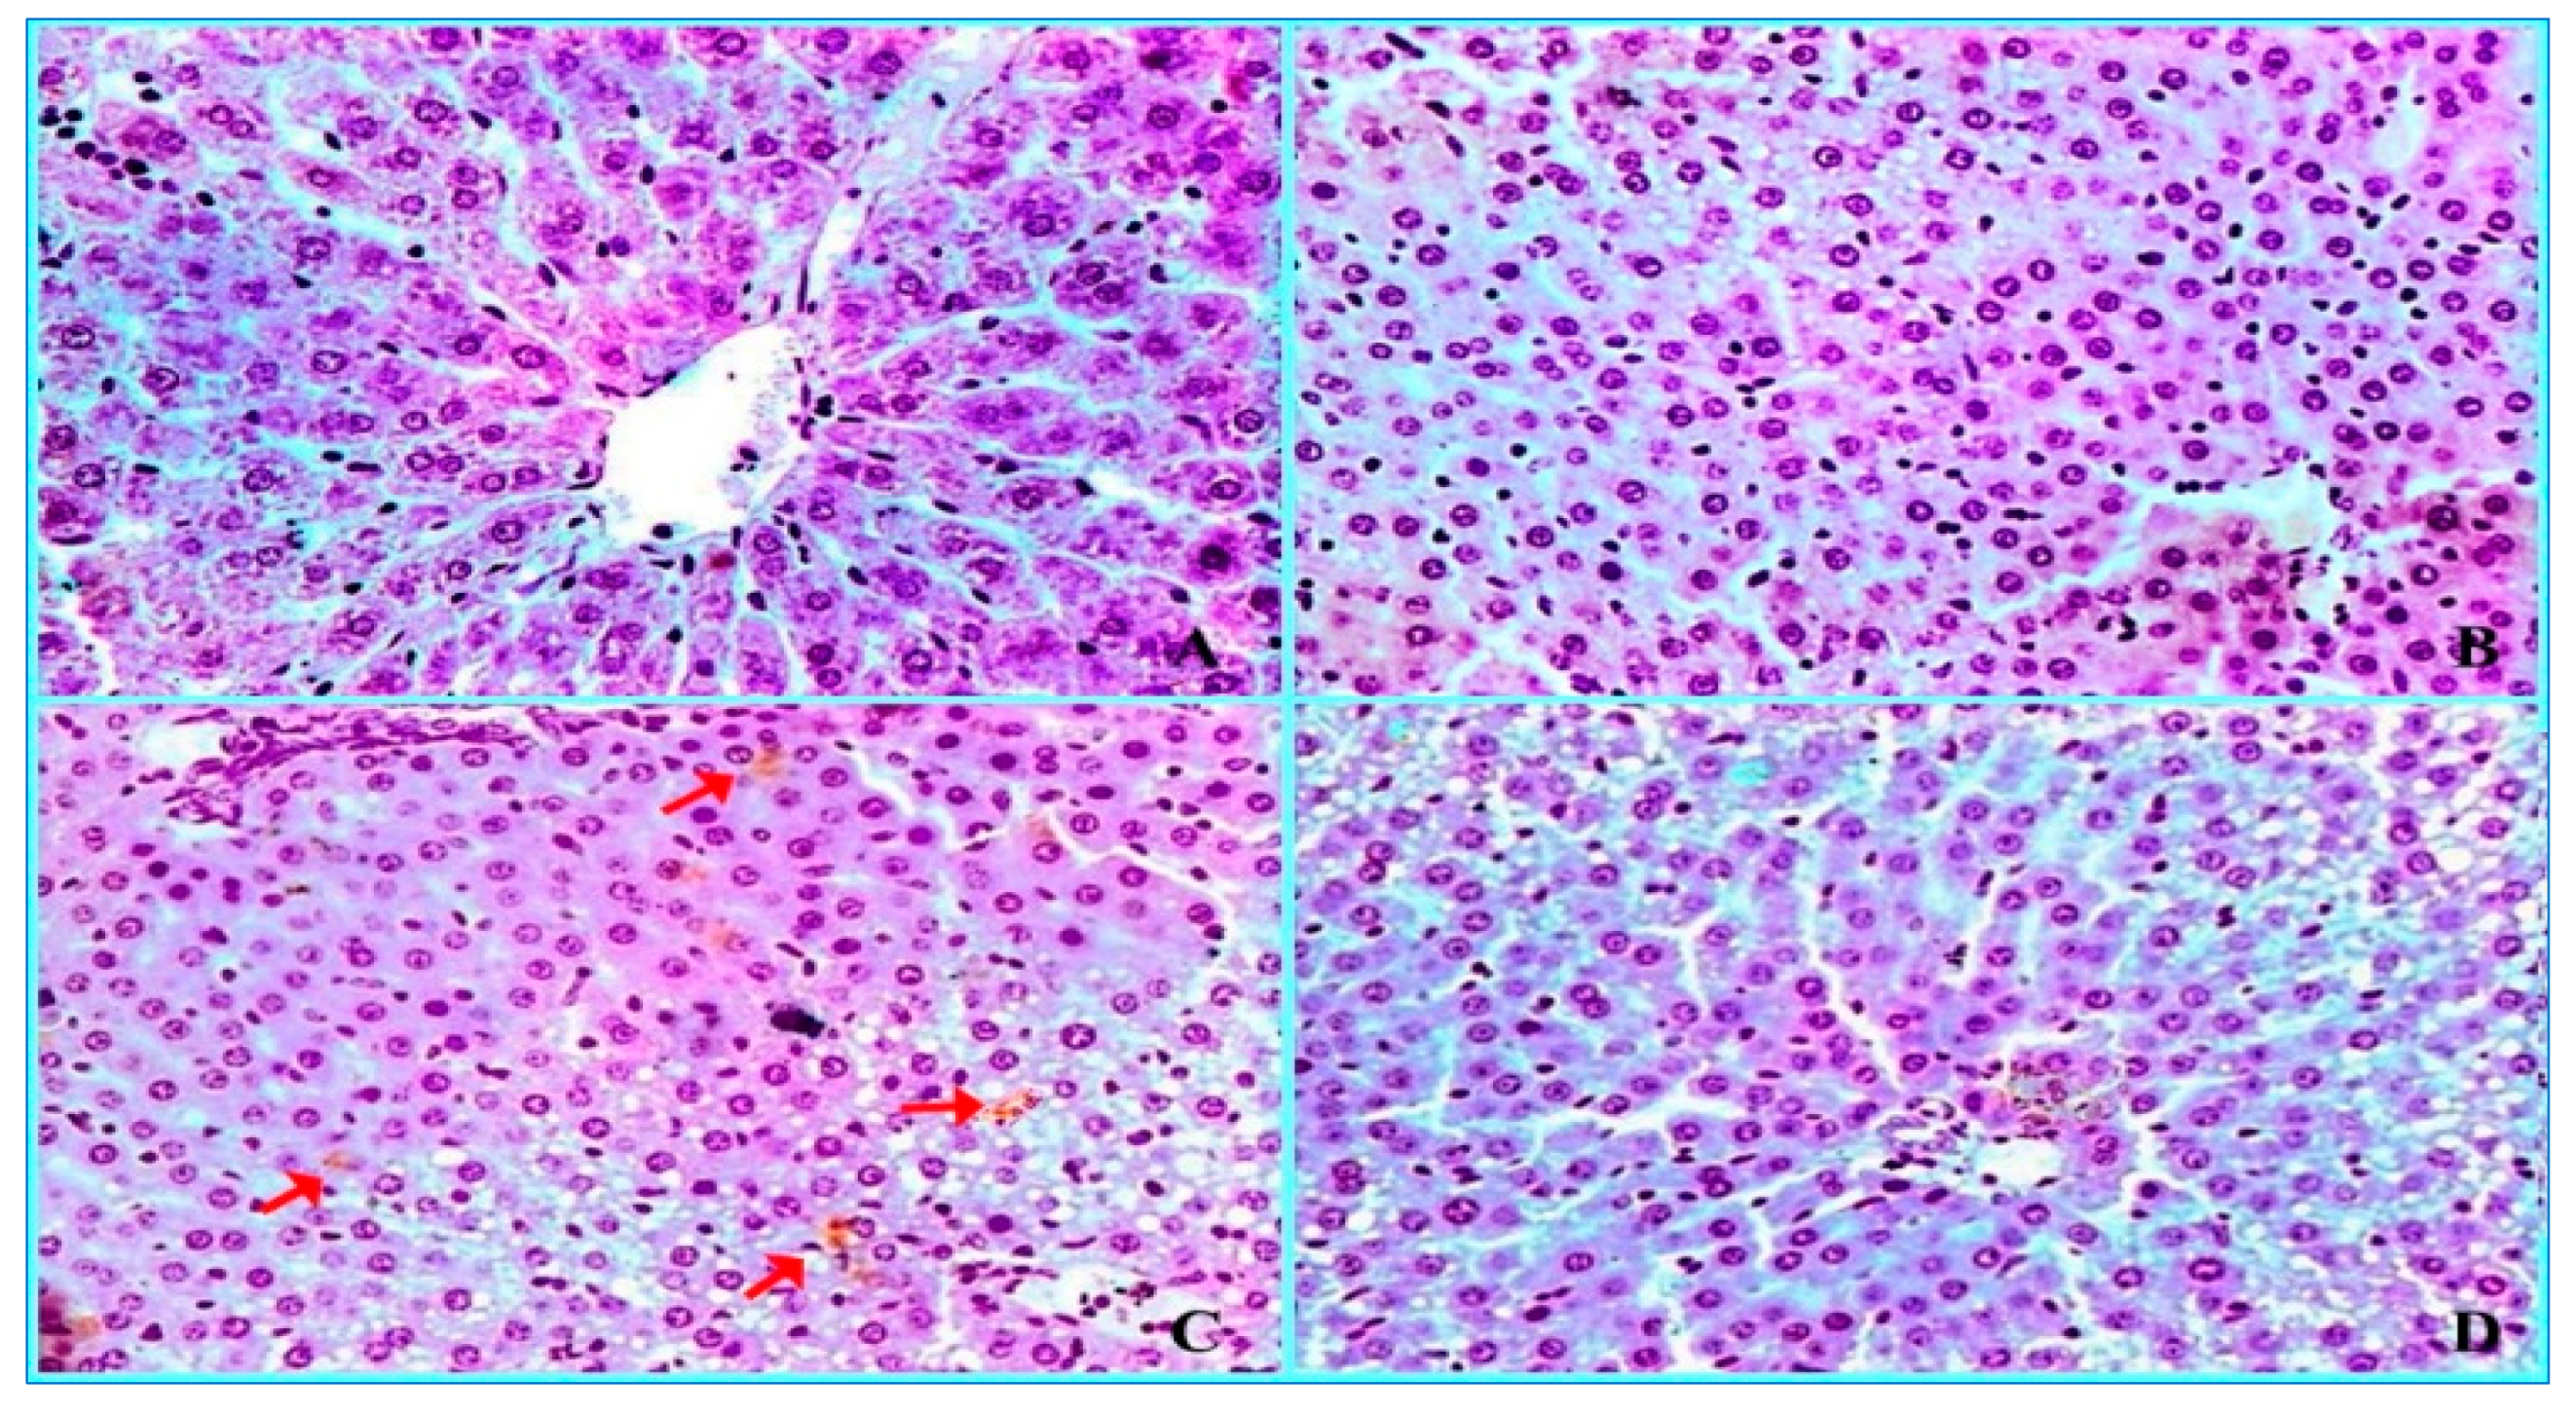

2.3. Histopathological Findings